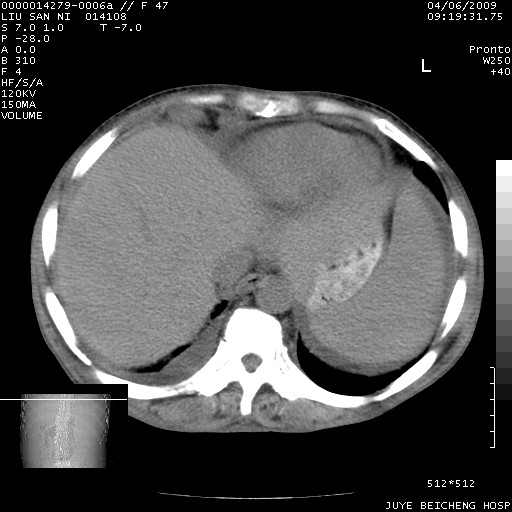

以下是引用前行在2009-4-7 10:31:00的发言:[br]肝脾肿大;双肾增大,双肾盂少量积水可能,肾膜膜增厚,肾周间隙增宽,并见桥间隔,提示结缔组系统疾病、系统性红瘢狼疮肾可能性大。继发右侧胸腔、心包、腹腔积液。